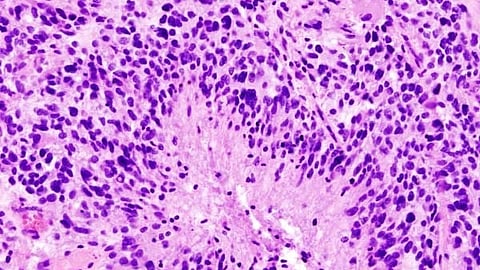

A pair of research articles published May 9 in Nature Genetics shed new light on the cellular complexity of glioblastoma, the most aggressive type of brain cancer. An international team of scientists, including researchers at the Yale Cancer Center, analyzed tumor samples from 59 glioblastoma patients to better understand how diverse cell types within a tumor change over time and in response to standard therapy. Their findings identify previously unrecognized patterns of cancer cell activity and may help guide future treatment strategies for this disease.

The first article[1] presents a detailed analysis of 121 primary and recurrent glioblastoma samples from the 59 patients to discover cancer cell types not previously identified in earlier, smaller studies. The large data set included about 430,000 cells and led to the identification of three novel glioblastoma cell “states,” in addition to confirming previously identified ones, that may contribute to a glioblastoma’s ability to adapt and evade therapies.

Glioblastoma is different from patient to patient and its cellular composition is varied even within the same tumor. Despite this variability, the researchers found some common cellular programs across patients that are influenced by specific gene mutations and a tumor’s surrounding cells. These common patterns define three overarching “ecosystems” that reflect distinct cellular communities.